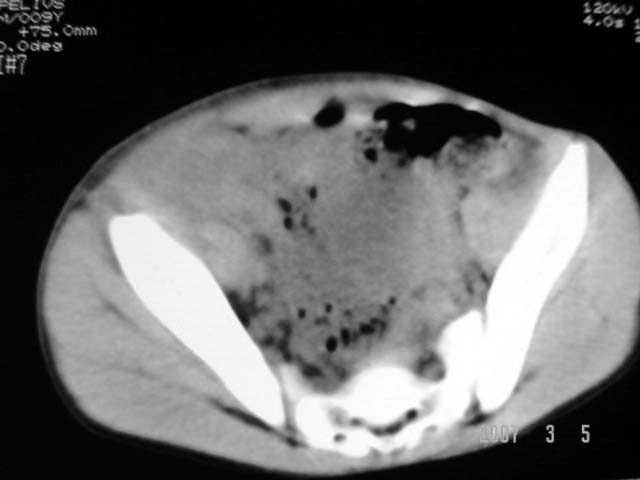

以下是引用dyqct在2007-3-5 10:28:00的发言:[br]右髂窝肿块。[br][br][br][br]